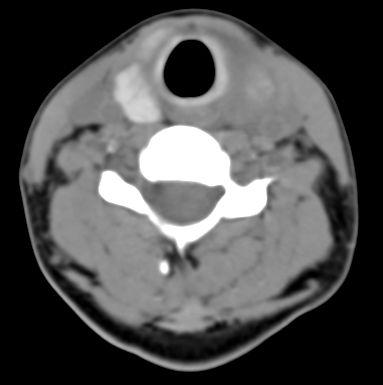

标题: CT9717:F、30Y、颈部左侧包块半年,压痛.患者拒绝作增强。 [打印本页]

标题: CT9717:F、30Y、颈部左侧包块半年,压痛.患者拒绝作增强。

请各位老师帮忙看看左侧甲状腺病灶!

左侧甲状腺增大,密度降低,性质不好定,还是作个增强,或作核素扫描.

甲状腺弥漫增大,以左叶明显,内见不均匀低密度影,边缘模糊欠清,周围脂肪间隙模糊。

结合病史:考虑亚急性甲状腺炎可能性大。(不知道病人有没有检测tsh t3 t4)

左侧甲状腺及甲状腺狭部弥漫性增大,边缘模糊,未见明确界线.考虑甲状腺炎可能性大.

左侧甲状腺弥满性增大,其内密度均匀减低,气管无受压。周围结构清晰。考虑甲状腺炎可能性大。

甲状腺弥漫增大,以左叶明显,左侧内见不均匀低密度影,边缘模糊欠清,周围脂肪间隙模糊。

1,病灶弥漫无明确边界.2,密度较均质.3,临床压痛明显.

2,亚急性甲状腺炎.临床多见,发病年龄较轻,由上呼吸道感染或病毒性腮腺炎后发病.临床触痛明显.然局部皮肤无红热.t3t4早期升高,后期降低.病灶可单侧或双侧.易炎性渗出,使脂肪密度增高.

3,桥本甲炎(慢性淋巴细胞性甲炎);自身免疫有关.t3t4降低.中老年女性多见.甲状腺弥漫增大,基本对称.,峡部最明显.边界较清.